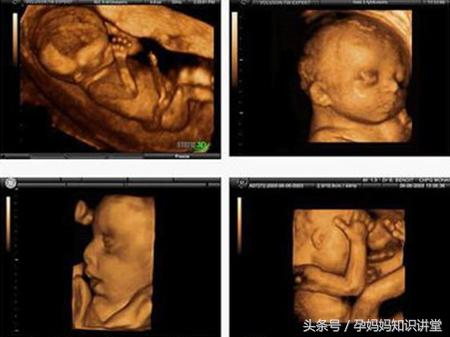

四维彩超提供了包括腹部、血管、小器官、产科、妇科、胎儿彩超图泌尿科、新生儿和儿科等多领域的多方面的应用。其结果是:能够显示您未出生的宝宝的实时动态活动图像,或者其它人体内脏器官的实时活动图像。